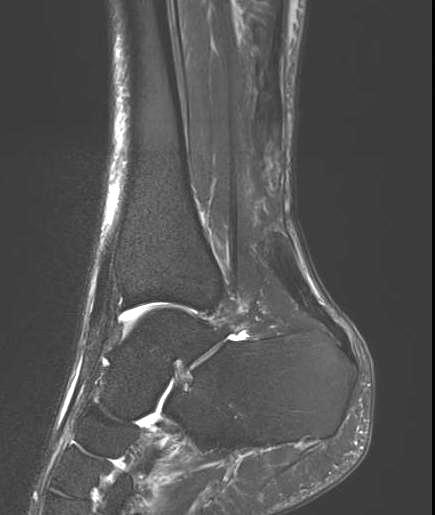

MRI

Indication

- incomplete rupture / clinical uncertainty

- chronic tears - measurement of gap for reconstruction planning

Acute

High grade partial thickness

Chronic retracted

New incomplete tear seen on MRI

Rerupture with scar tissue between tendon ends